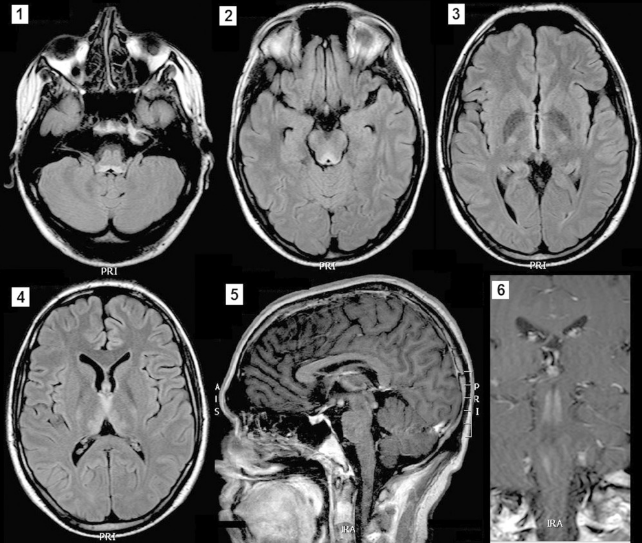

Диагностика заболевания происходит на основании результатов МРТ, клинической картины, анамнеза и данных лабораторной диагностики.

1 — гиперинтенсивный сигнал не только от периакведуктального серого вещества и маммилярных тел, но и белого вещества среднего мозга.

2, 3 — гиперинтенсивный сигнал от отдельных участков серого вещества коры головного мозга.

4 — участок центральной демиелинизации в области среднего мозга и верхней части варолиева моста.

5 — накопление контраста в оболочках мозга и отдельных участках коры [4].

Так, при МРТ головного мозга может выявляться поражение определенных участков серого вещества, в данном случае поражено серое вещество покрышки среднего мозга. Почти всегда при синдроме Вернике-Корсакова выявляется поражение мамиллярных тел, данный снимок не является исключением. На изображении также видно поражение гиппокампа и гипоталамуса с незначительным накоплением контраста в этих областях, также характерное для СВК.